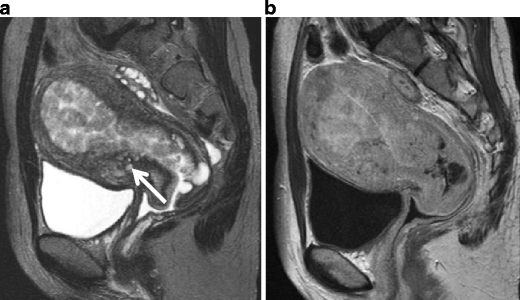

Adenosarcoma in a 27-year-old woman. a Sagittal T2-weighted image shows adenosarcoma composed of numerous polypoid mass, which protrude into the endometrial cavity. Multiple punctate foci of high intensity within the tumor represent microscopically dilated glands in the tumor. The disruption of the endometrial-myometrial border and heterogeneously increased intensity in the anterior wall represents invasion of the tumor into the myometrium (arrows). b Postcontrast T1-weighted image shows good enhancement in the tumor

Carcinosarcoma in a 66-year-old female. a T2-weighted image demonstrates a large polypoid tumor (arrowheads) of heterogeneously high intensity, containing fresh hemorrhage of distinct low intensity. The tumor protrudes into the cervical canal. Fluid-fluid level in the uterine cavity represents hematometra. b T1-weighted image shows area of high intensity (arrow) in the tumor, suggesting intratumoral hemorrhage. c Postcontrast T1-weighted image shows fine reticular enhancement in the lesion (arrowheads)